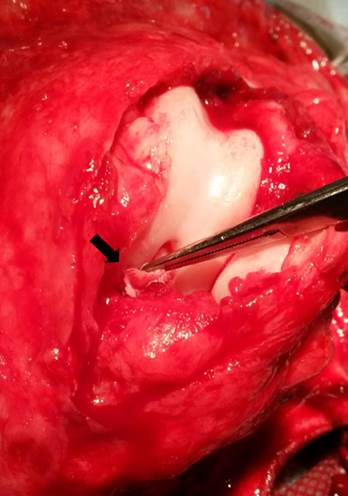

En este trabajo se presenta el reporte de 15 caninos de raza cimarrón uruguayo, diagnosticados e intervenidos quirúrgicamente por RLCA, en una clínica particular, durante los años 2018 y 2019. Durante la anamnesis se registró el tiempo que había transcurrido desde el comienzo de los síntomas hasta el momento de la consulta, así como los tratamientos realizados. El diagnóstico presuntivo de la RLCA, en todos los casos, se realizó mediante el examen clínico traumatológico, incluyendo la prueba de cajón, la prueba de compresión tibial, constatándose la inestabilidad de la articulación. Además, se realizaron radiografías (Figura 2), que mostraron diferentes signos de artrosis de la rodilla. Se evaluó el grado de artrosis mediante la Escala Bioarth. Todos los animales fueron pesados y se evaluó el grado de claudicación en el momento de la primera consulta, según el método descrito por Selmi et al., (2002). La confirmación definitiva de la lesión de la ruptura del LCA se realizó por medio de la artrotomía lateral de la rodilla descrita por Vasseur (2006) (Figura 3:).